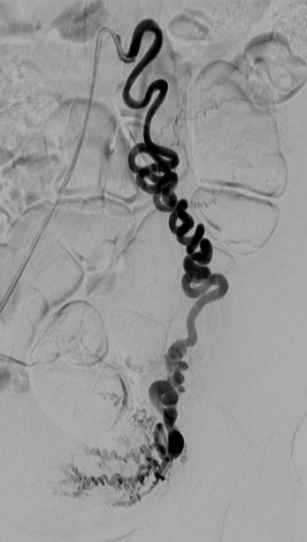

![]() 双侧子宫动脉发育不良 双侧卵巢动脉栓塞术 - 500 - 900 微米 未出现卵巢功能衰竭 ![]() 约10%-15%的患者在接受UAE后未见明显改善,其中一些病例可能是因为卵巢动脉提供了额外的血供。 文章通过回顾六例患者的治疗经验,探讨了卵巢动脉栓塞术(OAE)作为子宫动脉栓塞术(UAE)补充疗法的可行性和效果。研究发现,OAE能够成功地使肌瘤缺血坏死,并且大多数患者在术后症状有所改善。尽管存在技术挑战,但OAE似乎是安全有效的。此外,所有接受OAE治疗的患者均保留了正常的月经周期,这表明该手术可能不会导致卵巢功能丧失。然而,由于样本量较小,目前的研究结果尚不足以得出明确结论,需要进一步的研究来验证这些发现。 ![]() 评估在有卵巢动脉参与供血的症状性子宫肌瘤患者中,进行卵巢动脉栓塞术的安全性及临床结局。 共13名患者,均有症状性子宫肌瘤,且MRI或血管造影显示有卵巢动脉参与供血。并在初次或二次进行补充卵巢动脉栓塞术。

所有年龄超过 40 岁的患者, 卵巢受损 14%-43% 研究中闭经发生率(15%)与单纯UAE报告相似,可能与患者年龄(≥45岁)及卵巢储备自然下降有关。 ![]() 50岁,长期因子宫肌瘤导致月经出血过多,痛经和贫血。 子宫肌瘤栓塞术前,显示双侧子宫动脉发育不全,子宫肌瘤双侧卵巢动脉。 经皮股动脉穿刺双侧卵巢动脉栓塞,先500μm-700μm emboSphere 微球 术后4周,和6月的中短期随访,月经正常,子宫容积减少,贫血纠正,无卵巢功能衰竭。但看起来非灌注容积较少。 术后9月,由于子宫肌瘤持续存在,患者自己希望绝经,行全子宫和双侧卵巢切除术 术后病理,子宫内可见栓塞微粒伴有坏死,卵巢内也见栓塞微粒,但卵巢功能未受损。